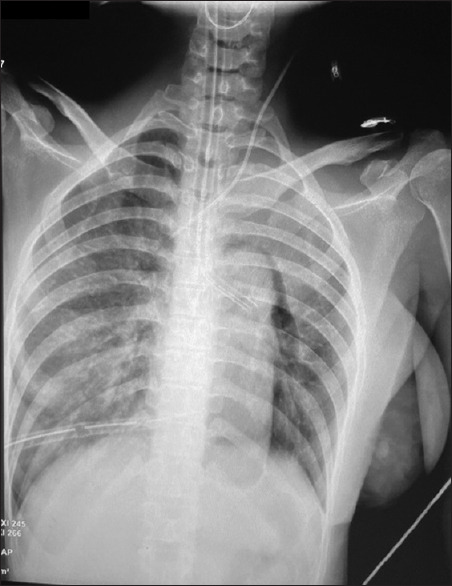

Abstract: Re-expansion pulmonary edema (RPE) is a rare complication of minimally invasive cardiac surgery (MICS). We present a case of RPE following atrial septal defect (ASD) closure using a thoracotomy approach and cardiopulmonary bypass (CPB). REP contributes to significant morbidity and extends the length of stays in the intensive care unit. Understanding the pathophysiology and risk factors of RPE allows us to prevent or minimize the incidence.

Abstract Image